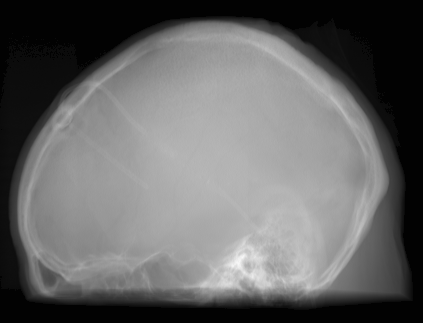

(a) Guide 𝑮𝑮\boldsymbol{G}

Refer to caption

(b) Input 𝑰𝑰\boldsymbol{I}

(c) Guidance map 𝑴𝑴\boldsymbol{M}

(d) Prediction 𝑷𝑷\boldsymbol{P}

(e) Ground truth

(f) Guide 𝑮𝑮\boldsymbol{G}

(g) Input 𝑰𝑰\boldsymbol{I}

(h) Guidance map 𝑴𝑴\boldsymbol{M}

(i) Prediction 𝑷𝑷\boldsymbol{P}

(j) Ground truth

Figure 2: Inputs and outputs of the guided filtering pipeline based on the WDSR network. T1 & T2 MRI pairs (a)-(e) and CT & MRI projection images (f)-(j).

In Fig. 2 and 4, exemplary input, output and label images of the pipeline are presented for both tasks. Additional super-resolved images for both network architectures with and without the guided filter can be seen in Fig. 3. The results show a consistently high quality over both, the tomographic and the projective domain, as well as both tasks. Corresponding quantitative evaluation can be found in Table I and II. For SR, the WDSR network, i.e., the designated super resolution network, performs consistently better for both datasets with and without the guided filter. Applied to the tomographic images, the approaches without the guided filter deliver slightly better quantitative results. For the projection images this difference diminishes and both approaches are on par. In the case of denoising, the approaches with the guided filter deliver a lower mean absolute error while the structural similarity is increased without it. Though, the measurable differences are only marginal. The results generated by the plain guided filter without the learned guidance map are numerically worse than the approaches empowered by the guidance map generator for all tasks. This observation is most prevalent when observing the results of the tomographic T1 and T2 Flair images for SR, while for denoising the results are closer to the deep learning-based approaches.

In general, the decrease in image quality metrics w.r.t. to smaller radii is much stronger for the tomographic T1 and T2 Flair images than for the projection images. We assume the reason for this to be the difference in resolution of both datasets. The projection images resemble the ground truth more closely from the outset when compared to the tomographic images as seen in Fig. 2(b) and 2(g), respectively. Consequently, more information has to be generated by the networks. As the guided filter is sensitive towards correlation between the input and guidance map the constraints on the applicable changes are more severe.